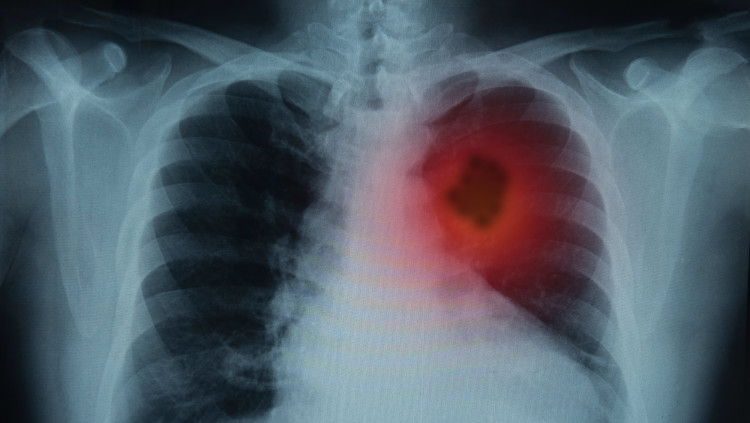

כך בינה מלאכותית יכולה להעריך את הסיכוי של אדם לחלות בסרטן ריאות